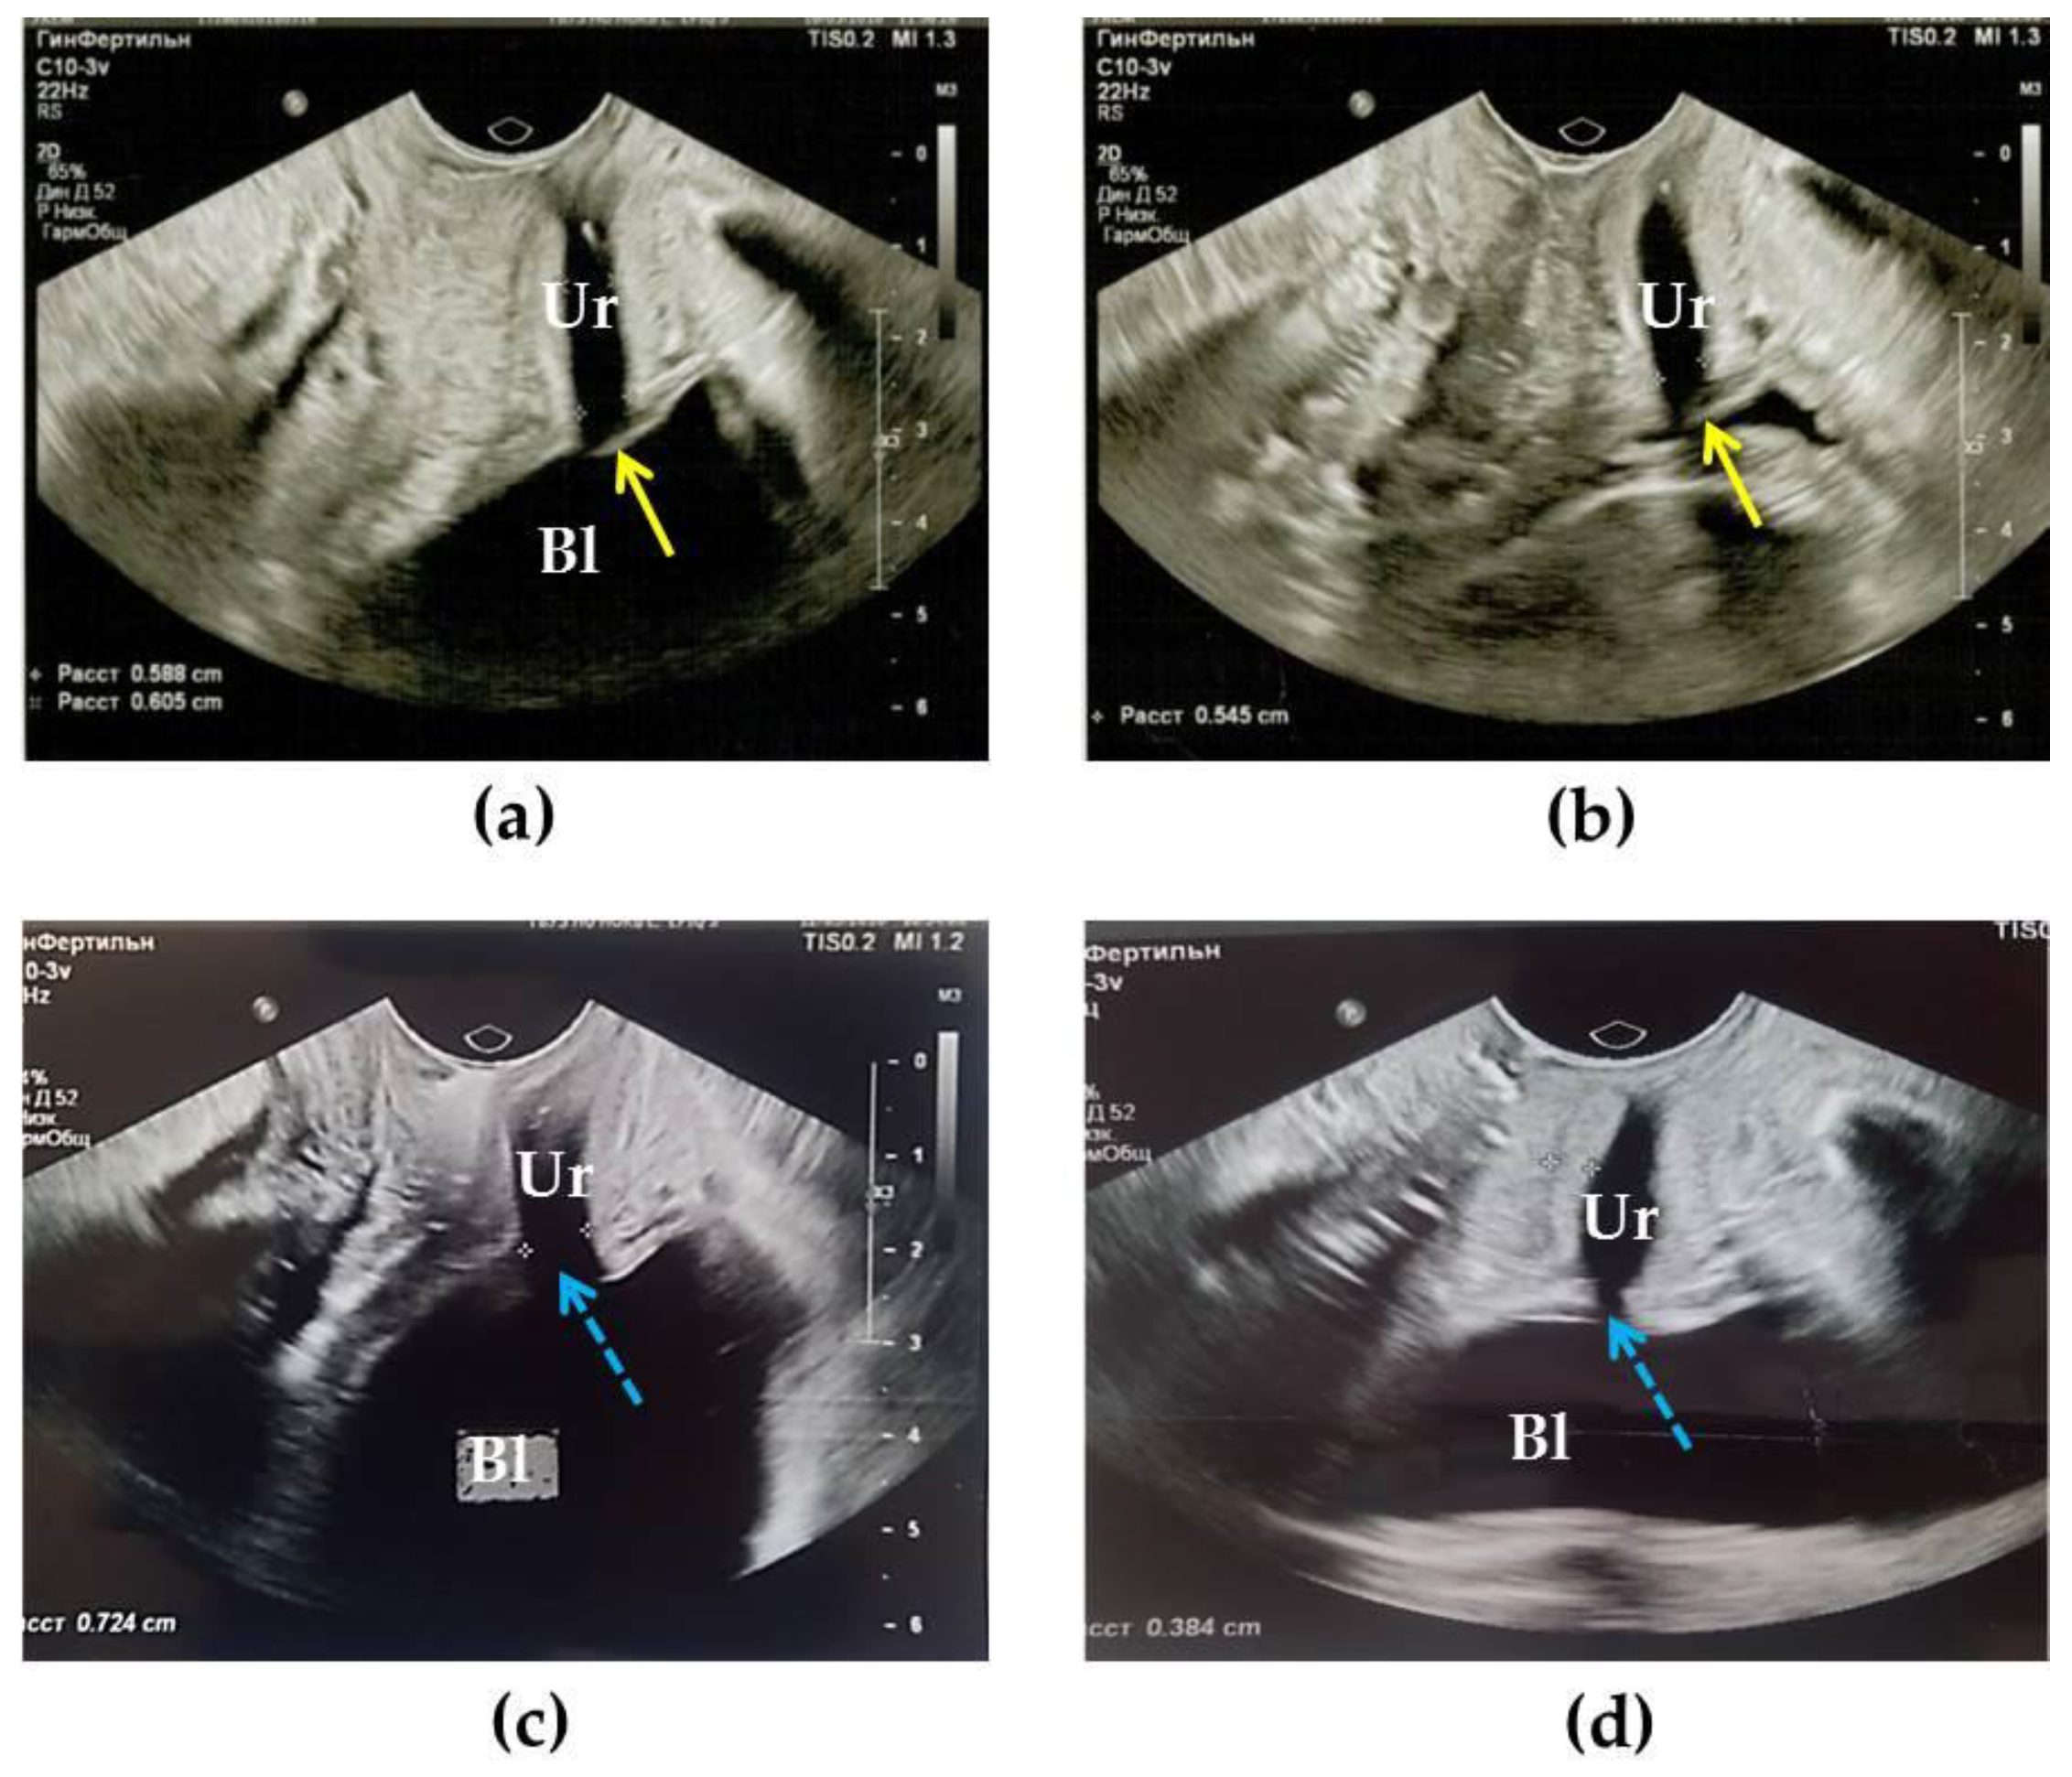

3.4. Results of TVUS Research

| 5. Transvaginal US/compression US | assessment of the size, shape, structure of the urethra and bladder neck/mapping of the urethral wall and surrounding tissues stiffness | 24 | 6 |